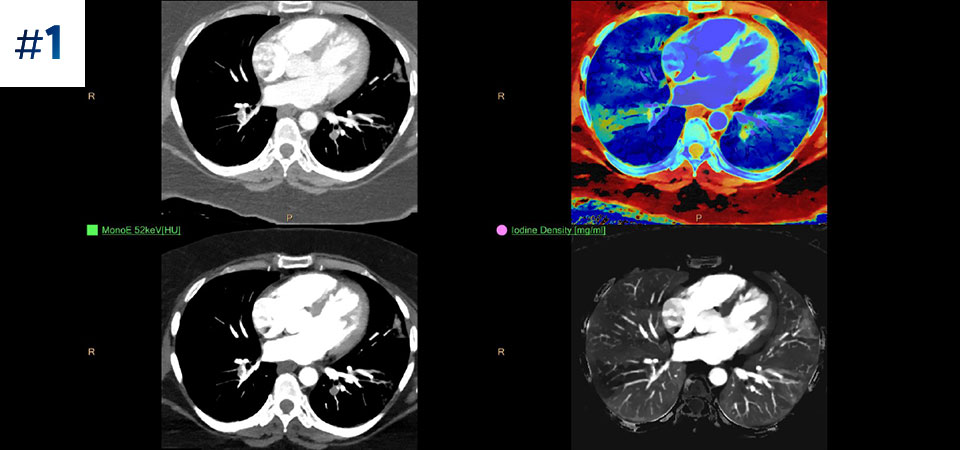

With detector-based spectral, you acquire multiple layers of data—conventional and spectral—within a single exposure and without special scan modes for improved tissue characterization and visualization.

Scan as usual A single scan for fast, low-dose conventional and spectral data for every patient, every time.

Always available 100% spectral, 100% of the time for results that are always available on-demand, even retrospectively.

Reduced follow-up exams Improved tissue characterization and visualization may reduce the need for follow-up scanning for sub-optimal exams and incidental findings.

Across patient types Benefits a wide range of patient types from pediatric to bariatric.